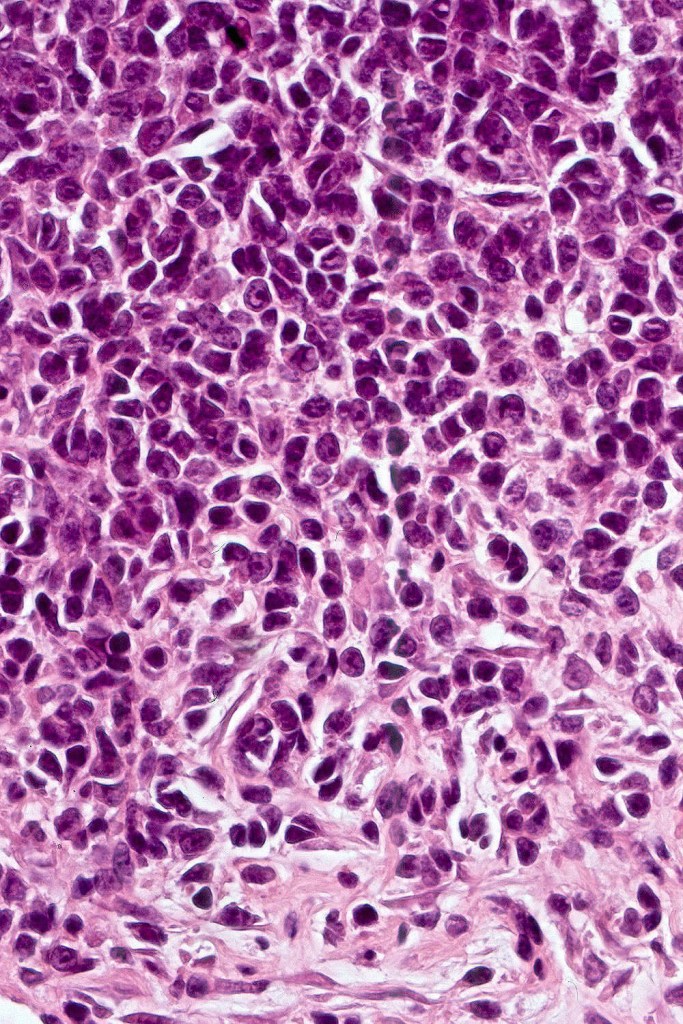

A rare variant of nevoid melanoma wherein the tumor cells have scant cytoplasm, and basophilic, hyperchromic nuclei mimicking type B nevus cells. Typically, the tumor cells are positive for S100, Mart-1 & HMB45. It is of no prognostic importance. It is one of the more often encountered melanoma variants in giant congenital nevi & can be mistaken for a congential nevus if the lesion is dismissed as benign at scanning magnification. In the absence of clinical history in metastatic lesions, the differential diagnoses of lymphoblastic leukemina/lymphoma, neuroendocrine carcinoma, small cell carcinoma, neuroblastoma, malignant perihperal nerve sheath tumor & Ewing’s sarcoma can be excluded with appropriate immunohistochemistry. Exceptionally small cell melanoma may express neuroendocrine markers